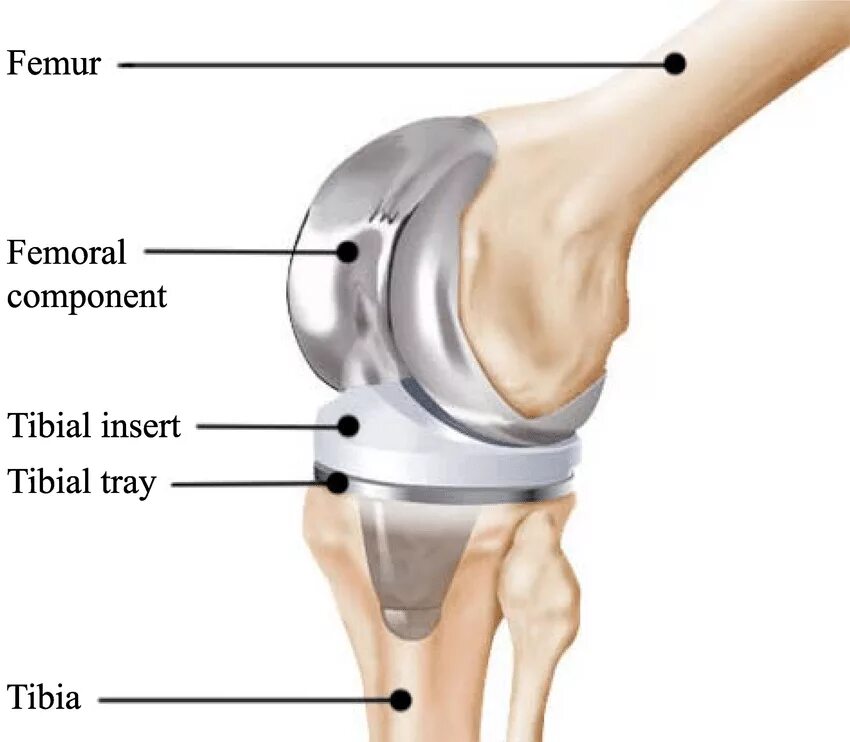

Как выглядит коленного